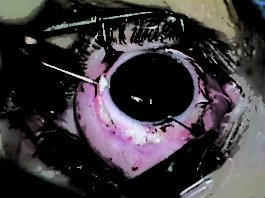

Le neoplasie palpebrali e perioculari

Riassunto

I tumori palpebrali sono la neoplasia più comune nella pratica oftalmologica quotidiana e comprendono un'ampia varietà di...

Melanoma oculare: manifestazioni cliniche e approcci terapeutici

I tumori dell’occhio sono una patologia rara e tra questi quelli clinicamente più frequenti sono il melanoma...